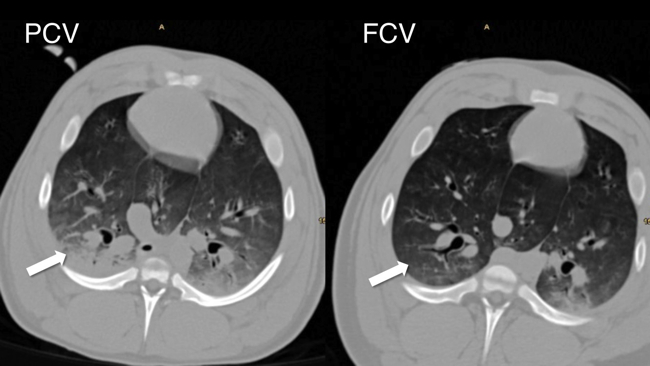

Our group investigates flow-controlled ventilation (FCV) as a novel ventilation method established to guarantee a continuous, constant and typically identical flow during inspiration and expiration. Additionally, the constant flow coupled with direct intratracheal pressure measurement allows accurate evaluation of dynamic compliance and adjustment of ventilation settings accordingly. Our first experimental pilot study demonstrated more efficient gas exchange and improved oxygenation as well as less atelectasis in individualised FCV compared with pressure-controlled ventilation (PCV) at the best standard of care during long term ventilation. Similar results were observed in an experimental model of single lung ventilation and in an experimental model of acute respiratory distress syndrome. Two clinical ventilation studies are currently being conducted in patients undergoing cardiac surgery and thoracic surgery with single lung ventilation, comparing individualised FCV with standard-of-care PCV.